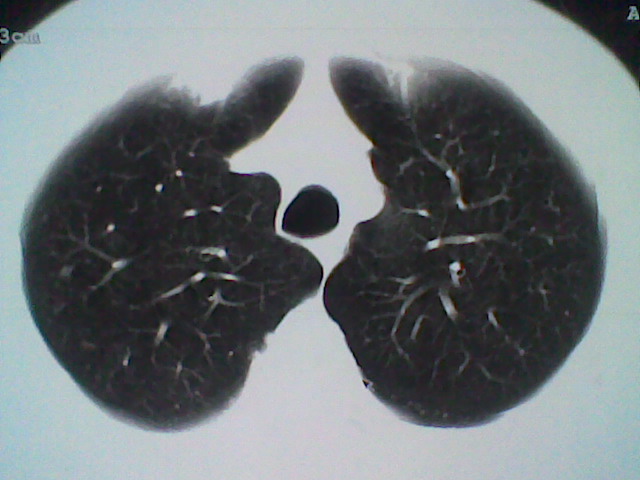

标题: CT21512:支扩伴感染?

患者女。咳嗽数天,咯血半天。

我们报的是支扩伴感染?

支持 支气管扩张并感染。

支持楼主意见,考虑支气管扩张并感染。

支气管扩张并感染。

支持楼主意见,还有肺气肿